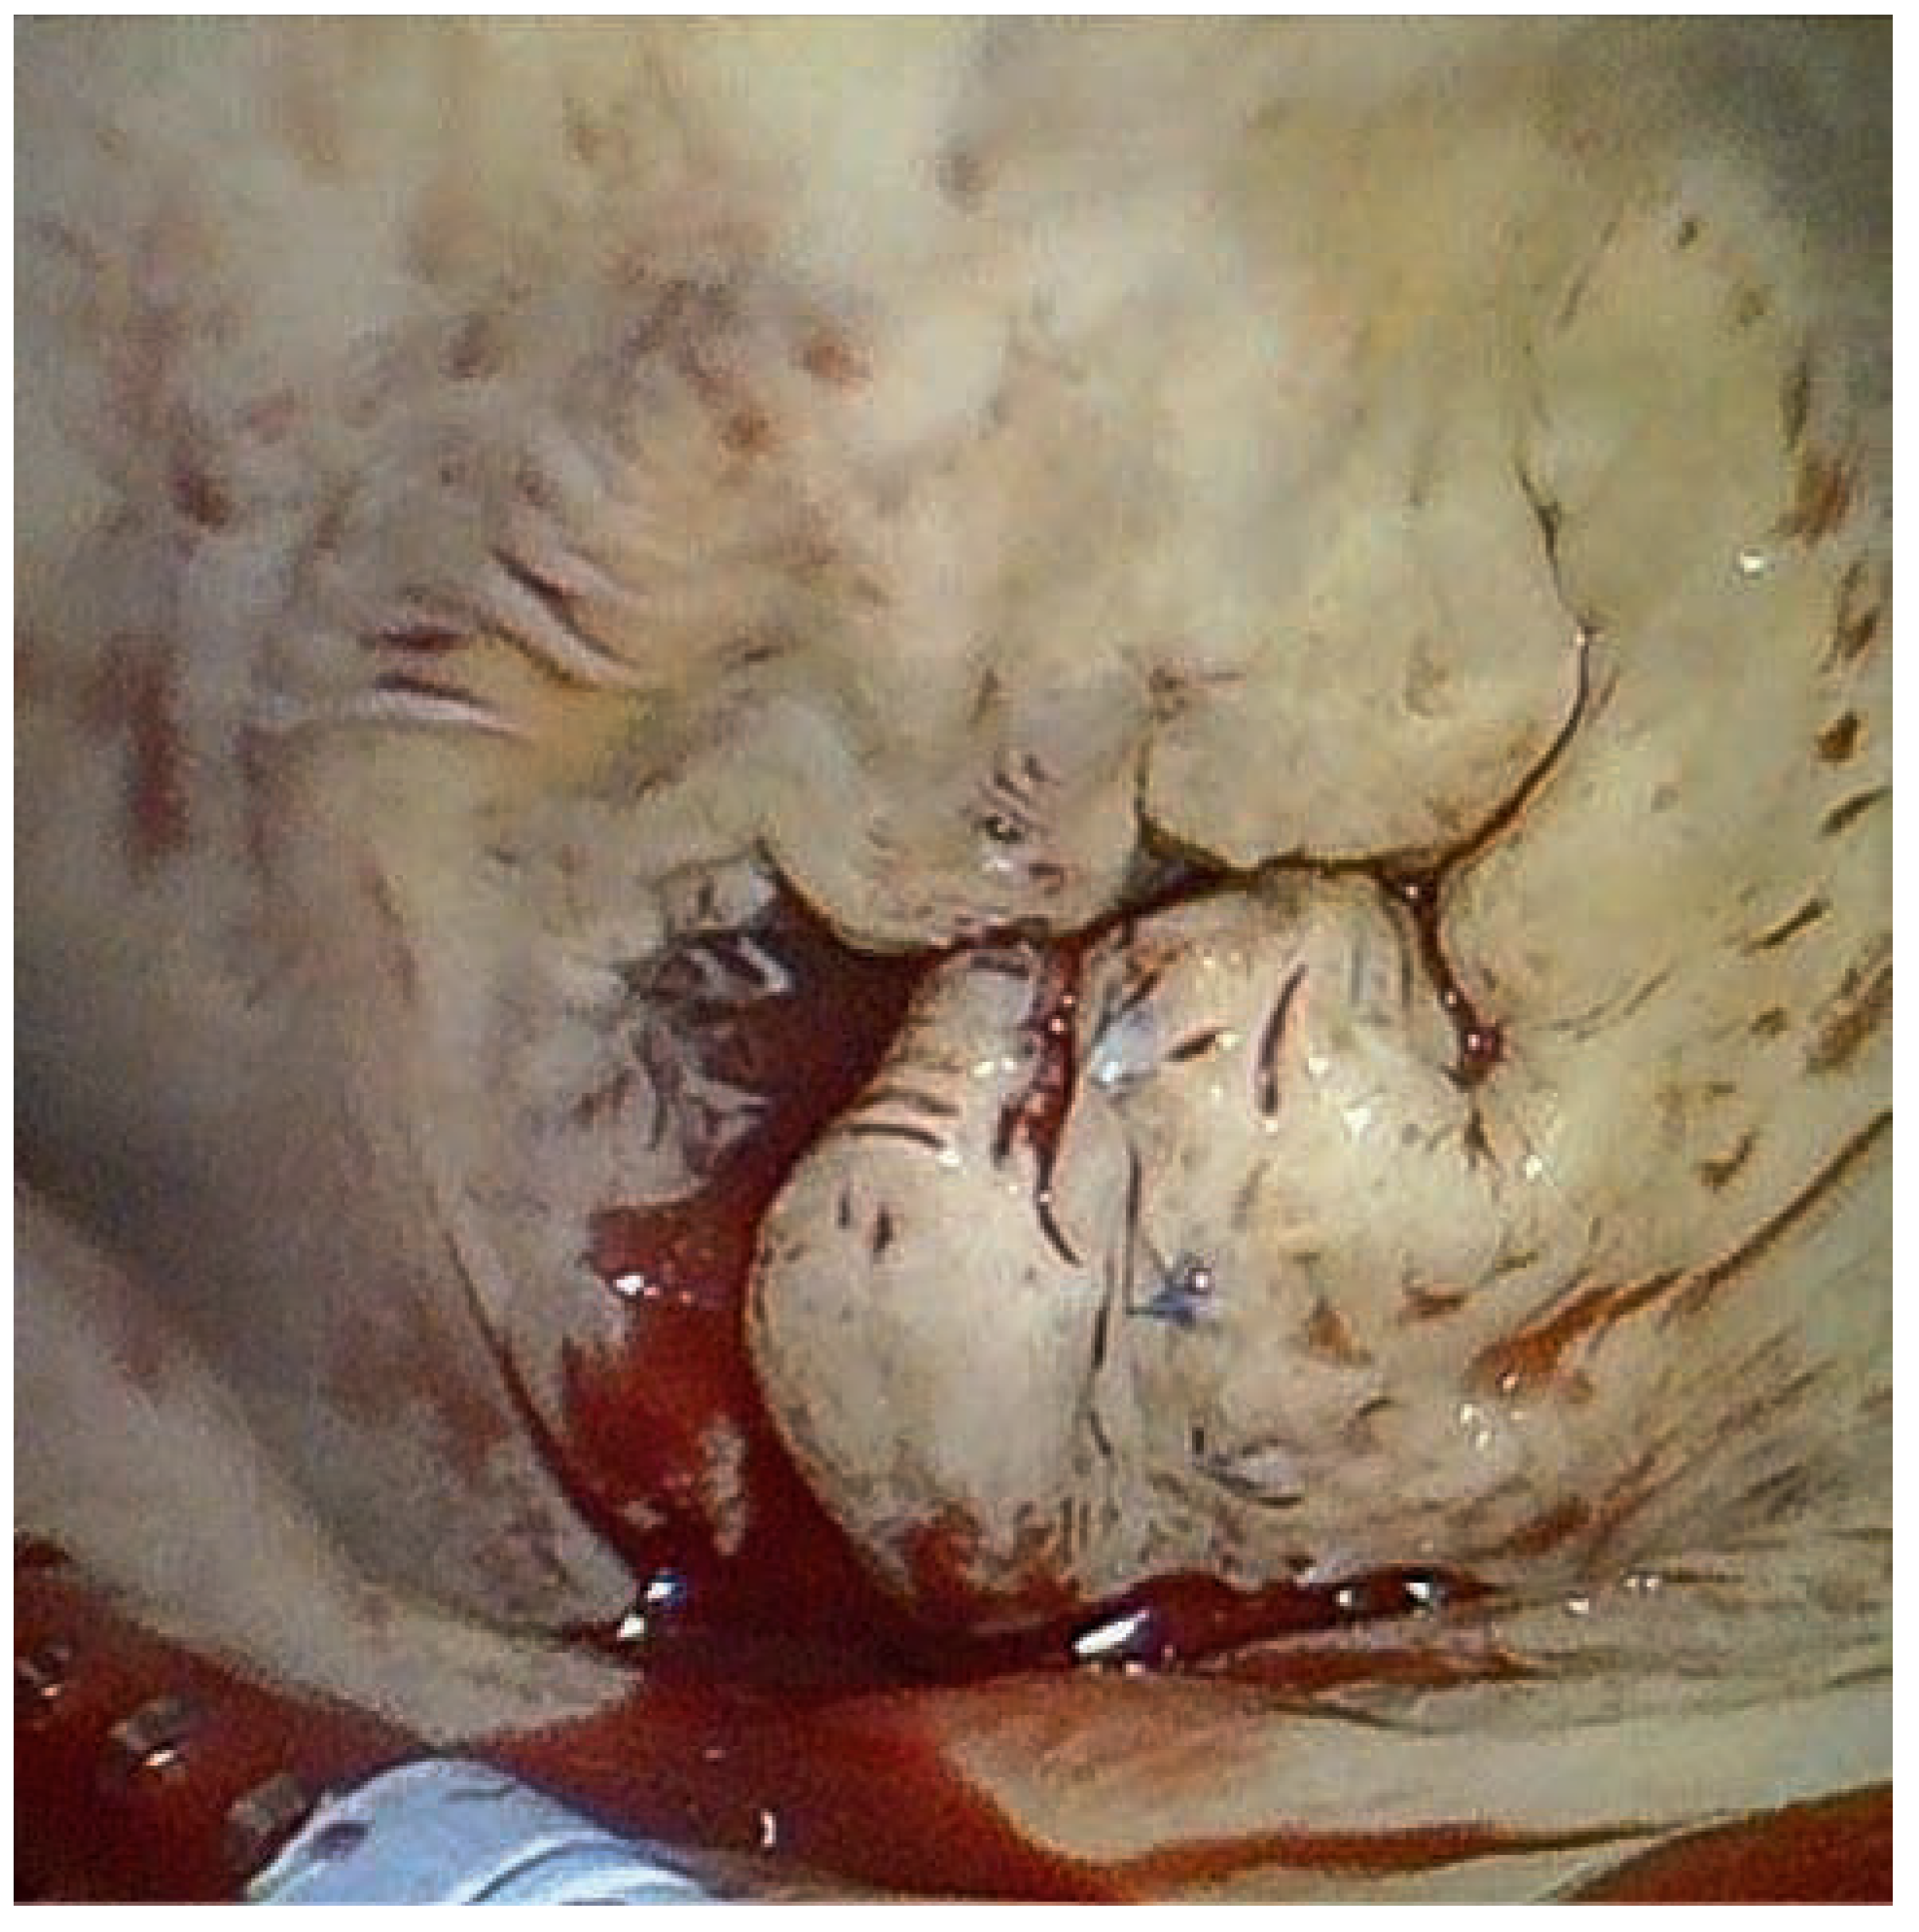

A 59-year-old man was referred to our institution for dyspnea. He had a history of mitral valve regurgitation with posterior leaflet valve prolapse. In 2006 he underwent mitral repair without annuloplasty ring implantation. In April 2012 dyspnea, NYHA II–III, recurred. Echocardiography showed grade III to IV mitral regurgitation. He was referred to another hospital, where percutaneous treatment with MitraClip™ implantation was proposed to the patient. Two MitraClips™ were implanted. Shortly after the intervention the patient complained about shortness of breath. He was seen at our hospital. Transthoracic echocardiography (Figure 1) and cardiac computed tomography (Figure 2) confirmed the clinical impression of both mitral stenosis and regurgitation with significant gradient and a valve surface of 1.7 cm2. M-mode echocardiography showed typical patterns of mitral stenosis (Figure 3). Mitral valve repair with annuloplasty could be performed with neocordals, reinforcement of the posterior leaflet and ring implantation (Figure 4 and Figure 5). Six months later, the mitral valve is fully functional and the patient is asymptomatic. This case is remarkable for a few points: firstly, mitral annuloplasty with ring implantation should be performed instead of simple repair. Secondly, equivalence of surgery with MitraClip™ implantation has been proven in some trials. However patients included in these studies were older and sicker than our patient. There are more arguments to suggest that MitraClip™ should be reserved for nonoperable patients or to patients refusing surgery. In our patient, revision surgery was probably a better option than a percutaneous approach. Valve dysfunction requiring a second intervention is almost 10 times more frequent after MitraClip™ implantation than after conventional surgery. Thirdly, even though trials about MitraClip™ are still ongoing, indications should not be lifted to younger patients, until we have clear evidence regarding the comparison of the 2 techniques. Finally, mitral valve repair with annuloplasty and ring implantation is possible after MitraClip™ implantation.

Figure 4. Perioperative stenosis with mitral valve ballooning. The MitraClip is visible on both leaflets.